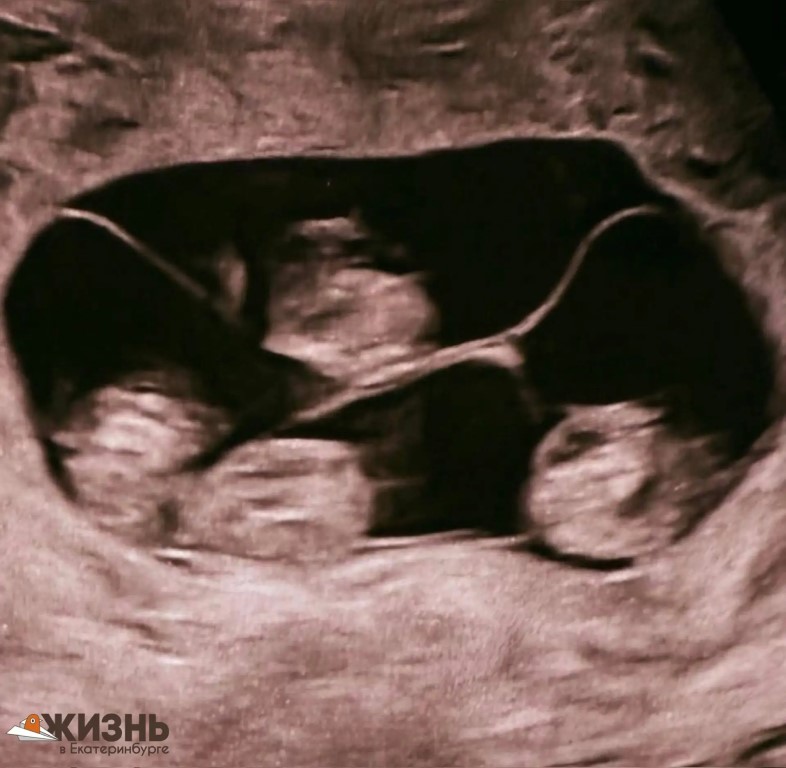

Фото 😳 1 шанс на 15,5 миллиона: в России родились 4 одинаковые девочки Впервые в стране зафиксировали уникальный случай — жительница Петербурга родила сразу 4-х полностью идентичных девочек. Вероятность такого события — примерно 1 на 15,5 миллиона родов. Сейчас малышки находятся под наблюдением врачей. Во всём мире известно всего около 15 таких случаев, и большинство — тоже девочки. Реакцию папы, кажется, можно не описывать 😅 Подпишись на канал